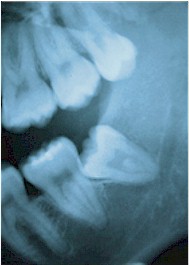

Εάν ο τρίτος γομφίος εμποδιστεί να ανατείλει στην φυσιολογική του θέση τότε ονομάζεται "έγκλειστος". Το δόντι αυτό μπορεί να είναι μερικώς έγκλειστο, δηλαδή ένα μέρος του μόνο ξεπροβάλει από τα ούλα ή μπορεί να είναι πλήρως έγκλειστο (εντελώς κάτω από τα ούλα). Σοβαρά προβλήματα μπορεί να προκύψουν από μερικώς έγκλειστα δόντια όπως πόνος, λοίμωξη, συνωστισμός ή και βλάβη στα γειτονικά δόντια. Πιο σοβαρά προβλήματα μπορούν να προκύψουν από τα πλήρως έγκλειστα δόντια εάν ο θύλακος (σάκος) που πάντα τα περιβάλλει γεμίσει με υγρό και εξελιχθεί σε κύστη.